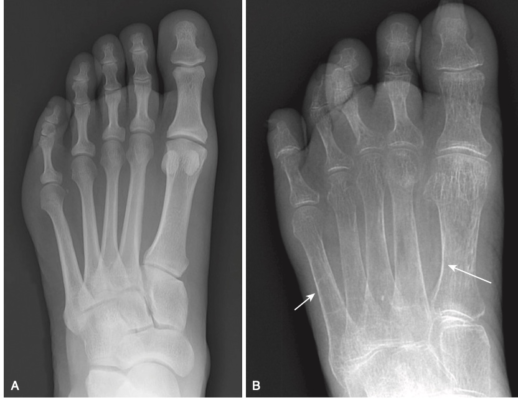

- Đường nối vỏ- tuỷ bình thường có thể nổi rõ, trong đó vỏ xương, mặc dù mỏng hơn bình thường, nổi bật hơn vì mật độ khoang tủy giảm (Hình -1).

- X quang thông thường tương đối không nhạy để dấu hiệu loãng xương. Phải mất gần 50% khối lượng xương trước khi có thể nhận biết được trên phim chụp X quang thông thường. Các dấu hiệu trên phim X quang thông thường bao gồm giảm chung mật độ xương, mỏng vỏ xương và giảm số lượng bè xương có thể nhìn thấy được trong khoang tủy.